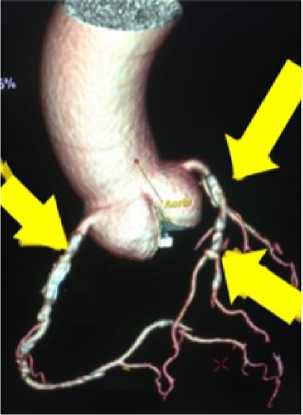

Учитывая полученные данные, принято решение о проведении МСКТ-КГ и артерий брахиоцефального ствола (БЦС) с контрастированием для верификации диагноза и определения дальнейшей тактики лечения. При контрастировании коронарных артерий и артерий БЦС выявлен гемодинамически значимый стеноз передней межжелудочковой ветви (ПМЖВ) до 75%, задней межжелудочковой ветви (ЗМЖВ) и диагональной артерии (ДА) до 90% (рис. 1), а также КТ-признаки сужения правой внутренней сонной артерии (ВСА) до 78% (рис. 2, 3).

Рисунок 2. 3D-реконструкция МСКТ-артерий БЦС. Стрелкой указан стеноз правой внутренней сонной артерии

Figure 2. 3D reconstruction of the MSCT arteries of the BCC. The arrow indicates stenosis of the right internal carotid artery

Рисунок 3. МСКТ артерий БЦС. Стрелкой указан стеноз правой внутренней сонной артерии Figure 3. 3D reconstruction of the MSCT arteries of the BCC. The arrow indicates stenosis of the right internal carotid artery